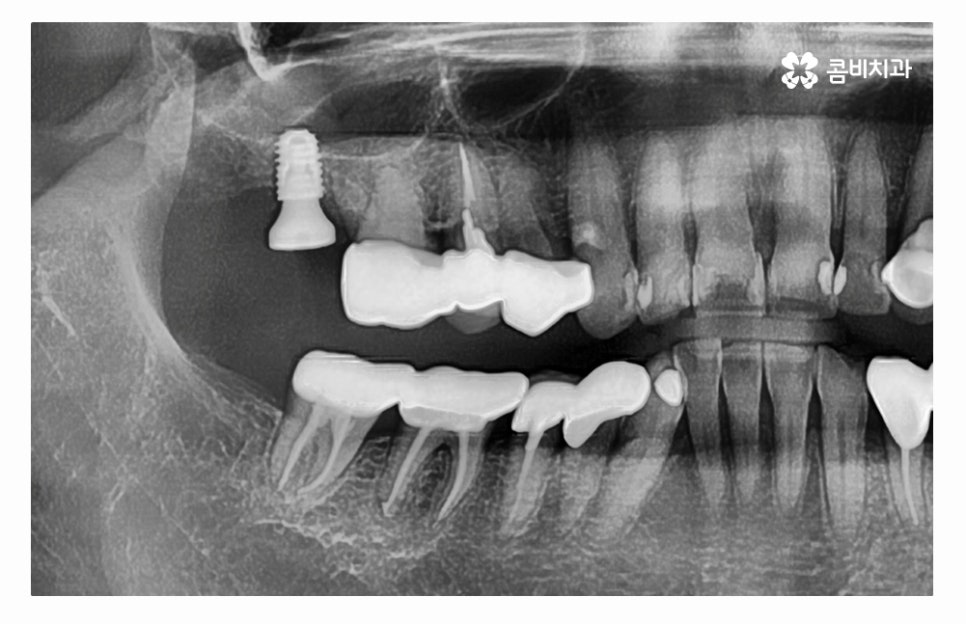

오늘 소개드릴 사례의 경우 충치로 인해 치아를 잃게 되었으며

발치 후 임플란트 수술을 통해 치아의 기능을 수복하였는데

치아를 잃게 되었을 때 원인을 잘 찾고 반복된 문제가 발생하지

않도록 정확한 진단이 필요하다고 할 수 있어요.

임플란트는 사후관리를 잘하면 반영구적인 사용도 가능한 만큼

초기 치료를 잘 받고 꾸준히 믿고 찾을 수 있는 치과를 신중하게 선택해야 하며

단지 저렴한 곳을 우선해서 찾기보다는 임플란트수술에 사용될

치과 재료부터 시설, 의료진의 경험과 실력 등을 잘 따져보실 필요가 있어요.

임플란트는 자연치아와 달리 치주 인대가 없고 신경이 없는 상태이기 때문에

주된 부작용이라고 할 수 있는 임플란트 주위염을 주의해야 하며

충치는 발생하지 않겠지만 청결 관리를 소홀하여 잇몸 건강이 나빠진다면

임플란트의 수명에도 악영향을 주기 때문에 각별히 주의하실 필요가 있어요.